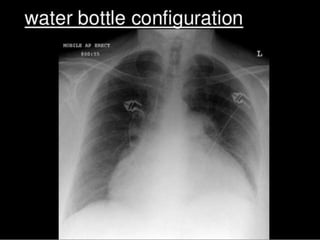

 Chest Radiography – enlarged cardiac silhouette

(water bottle heart) and pericardial fat stripe

INVESTIGATIONS  Baseline–CBC, Electrolytes,cardiac enzymes, ESR, CRP  Pericardiocentesis (diagnostic and therapeutic)  Pericardial fluid Analysis (R/E, C/S, Adenosine deaminase and Carcinoembryonic Antigen)  Thyroid profile  Rheumatoid Factor, Immunoglobulin complexes, Antinuclear Ab test  Chest Radiography – enlarged cardiac silhouette (water bottle heart) and pericardial fat stripe  CT scan and MRI